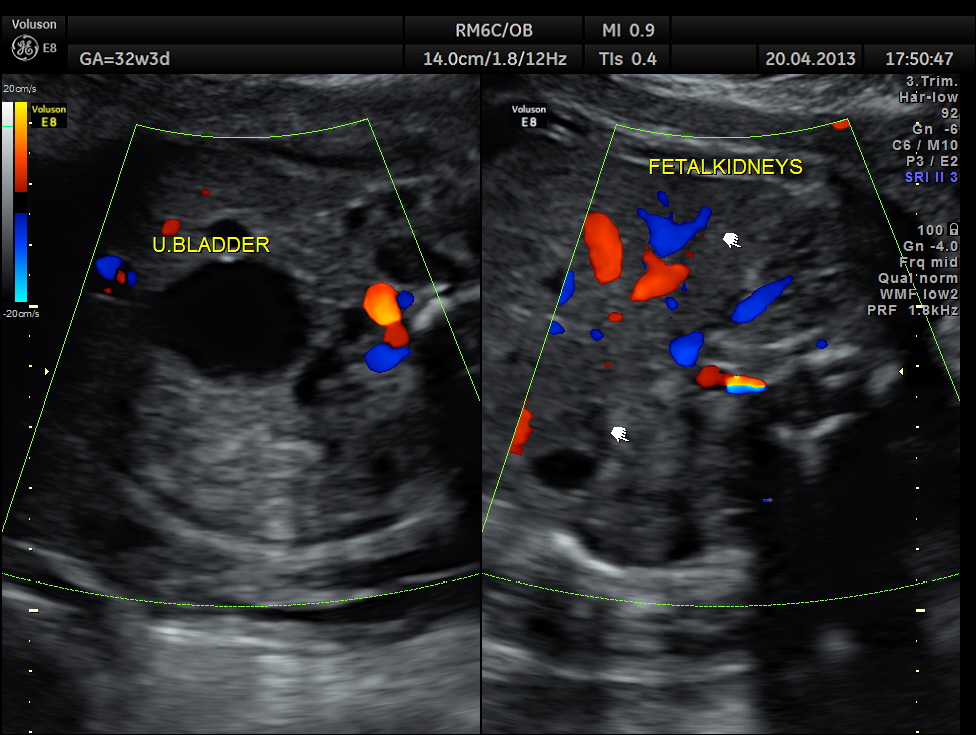

This was 26 year old lady, primigravida, without history of consanguinity.

Scan was done at 32 weeks of gestation. Earlier scans have been reported as normal.

The following images show bilateral renal pelvi ectasis and bilateral dilated ureters with all the changes more in the left kidney .

The left kidney also showed possible duple-ix pelvis with double ureters arising from them . But this finding could not be confirmed in all the views .